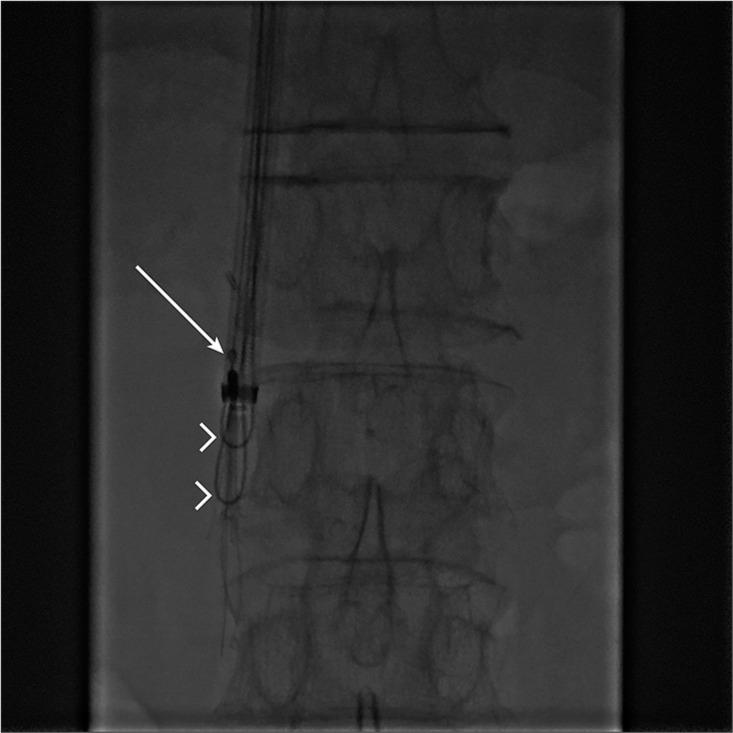

The aim of this report is to describe our experience in managing cases of difficult inferior vena cava (IVC) filter retrieval with emphasis on different advanced retrieval techniques. We report three cases of difficult IVC filter retrieval at our institution. We included three patients age ranging from 42 to 72 years. Two of the cases were presenting with the lower limb deep vein thrombosis and one of the cases had pulmonary embolism and they all had Retrievable Celect Platinum IVC filter (Cook Medical, Bloomington, Ind.) inserted preoperatively. One case was managed conservatively after failing IVC filter retrieval using standard retrieval set, meaning the filter was left in place, one was successfully removed with advanced endovascular retrieval techniques, and one failing advanced endovascular retrieval and finally had it removed with open surgery. We reviewed the risk factors contributing to difficult IVC filter retrieval and discussed the different options for managing these cases including conservative management, endovascular treatment, and open surgery for retrievable type of IVC filter which can be placed permanently. Knowledge of these options will help us better understand conditions, leading to difficult IVC retrieval on insertion, hopefully to minimize the occurrence of these cases, and to better manage cases with difficult IVC filter retrieval to decide the best option for each patient after careful consideration and multidisciplinary discussion with surgeons and patients.

本报告旨在描述我们在处理下腔静脉(IVC)滤器取出困难病例方面的经验,重点是不同的先进取出技术。我们报告了本院三例IVC滤器取出困难的病例。我们纳入了三名年龄在42岁至72岁之间的患者。其中两例患者表现为下肢深静脉血栓形成,一例患有肺栓塞,他们均在术前植入了可回收的Celect Platinum IVC滤器(库克医疗公司,印第安纳州布卢明顿)。一例在使用标准取出套件进行IVC滤器取出失败后采取了保守治疗,即滤器留在原位;一例通过先进的血管内取出技术成功取出;一例先进的血管内取出失败,最终通过开放手术取出。我们回顾了导致IVC滤器取出困难的危险因素,并讨论了处理这些病例的不同选择,包括保守治疗、血管内治疗以及对于可永久放置的可回收型IVC滤器的开放手术。了解这些选择将有助于我们更好地理解导致IVC取出困难的情况,有望尽量减少这些病例的发生,并更好地处理IVC滤器取出困难的病例,以便在与外科医生和患者进行仔细考虑和多学科讨论后为每位患者确定最佳选择。